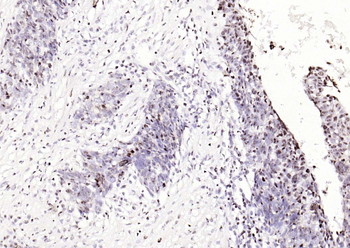

Phospho-Smad3 (Ser423 + Ser425) Rabbit Polyclonal Antibody [orb6983]

FC, IF, IHC-Fr, IHC-P, WB

Bovine, Canine, Equine, Gallus

Human, Mouse, Porcine, Rat

Rabbit

Polyclonal

Unconjugated

100 μl, 200 μl, 50 μlPhospho-SMAD5 (Ser463 + Ser465) Recombinant Rabbit Monoclonal Antibody [orb559123]